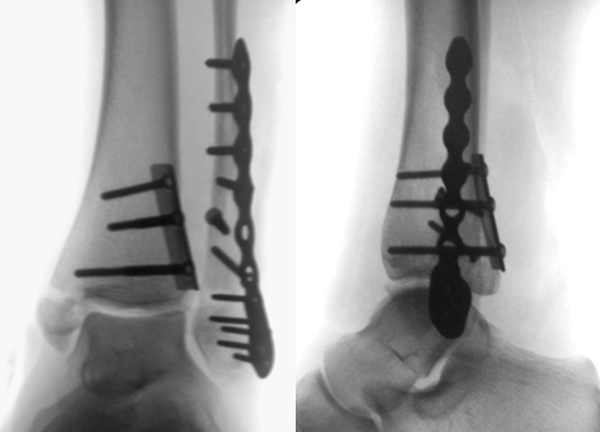

Die Versorgung von AO 44-B Frakturen erfolgt über einen längsverlaufenden lateralen Zugang. In der Regel gelingt eine suffiziente Stabilisierung mittels interfragmentärer Zugschraube (bei langem Frakturverlauf ggf. 2 Zugschrauben) und einer zusätzlichen Neutralisationsplatte (Abbildung 9 & 10).

Bei multifragmentären Frakturen (AO 44-B2.3) oder bei schlechter Knochenqualität sollte die Versorgung mittels winkelstabiler Plattenosteosynthese erwogen werden (Abbildung 11 & 12).